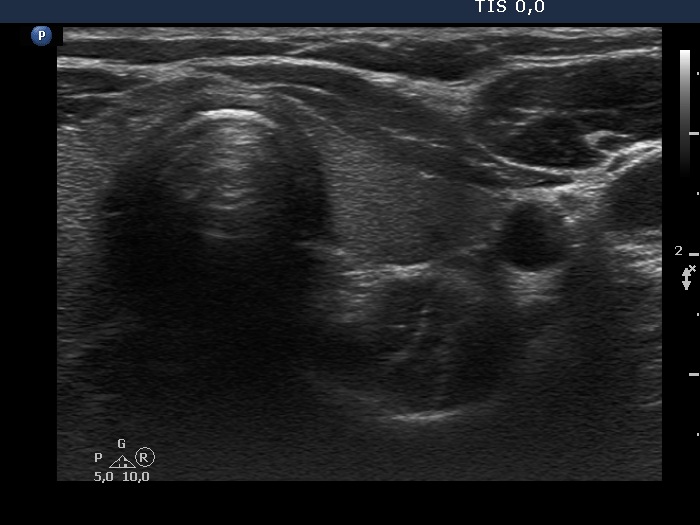

Ultrasonography. The thyroid was echonormal or minimally hypoechoic. There was a moderately hypoechoic nodule which had a cystic portion in the lower part. The nodule had lobulated margins and contained different hyperechoic figures. Beside figures caused either by posterior enhancement of proliferation of connective tissue, several ambiguous. bright granules were also found. Compared with the first measurement, the nodule is increased by more than 75% in volume.

Comment. It is worth looking at the video several times and analyzing the various echogenic foci.